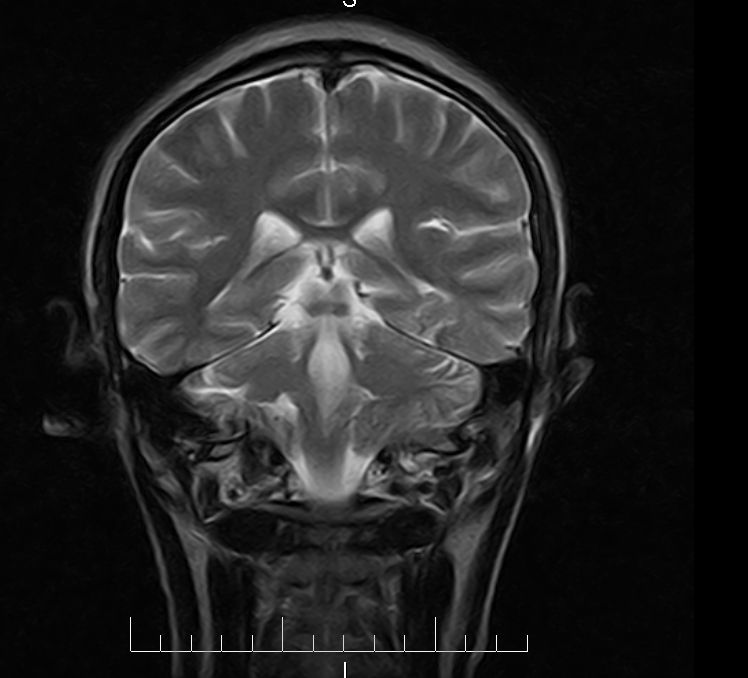

标题: MRI2379:30岁,男,癫痫10年,请各位看一下;CT示:左颞叶钙 [打印本页]

标题: MRI2379:30岁,男,癫痫10年,请各位看一下;CT示:左颞叶钙

左颞叶区见不规则点状混杂信号影

支持2楼 左颞叶区见不规则点状混杂信号影,考虑动静脉畸形。

考虑左侧颞叶脑血管畸形(avm)。----t1低等高混杂信号,t2等高信号周边较多流空血管影[冠状位明显],mra左侧大脑中动脉受压,远侧聚集.